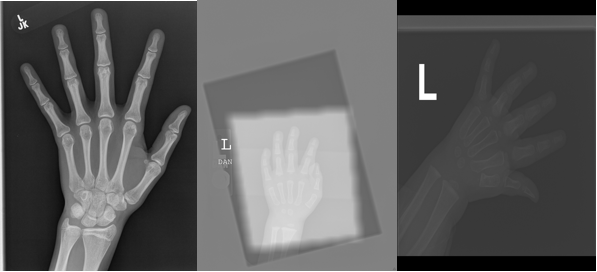

Transfer learning applies existing knowledge to a new domain. Although many methods take advantage of pre-trained ImageNet models to estimate the bone age, they do not consider the differences between training and testing data, which can sometimes be quite obvious, as shown in Fig. 1. The discrepancy of data (named data shift/bias) will cause a vulnerability in the trained model, which causes poorer generalization on test data [12, 13]. Transductive transfer learning uses both labeled training samples and unlabeled test samples to train the model and then uses a trained model to infer the label of the unlabeled test set. Hence, the data bias is mitigated via such a paradigm, which can improve the performance of the test data [14]. In this paper, we propose adversarial regression learning to estimate bone age and simultaneously reduce the data shift between training and test datasets.

As shown in Fig. 1, we observe differences between training and test data. Unlike previous work that only optimizes the model based on training data, we utilize the idea of transductive learning—we train the neural network using both the labeled training and unlabeled test data, which reduces the discrepancy between them. We adopt learning theory from [15] that the test risk can be minimized via bounding the training risk and discrepancy between them as follows.